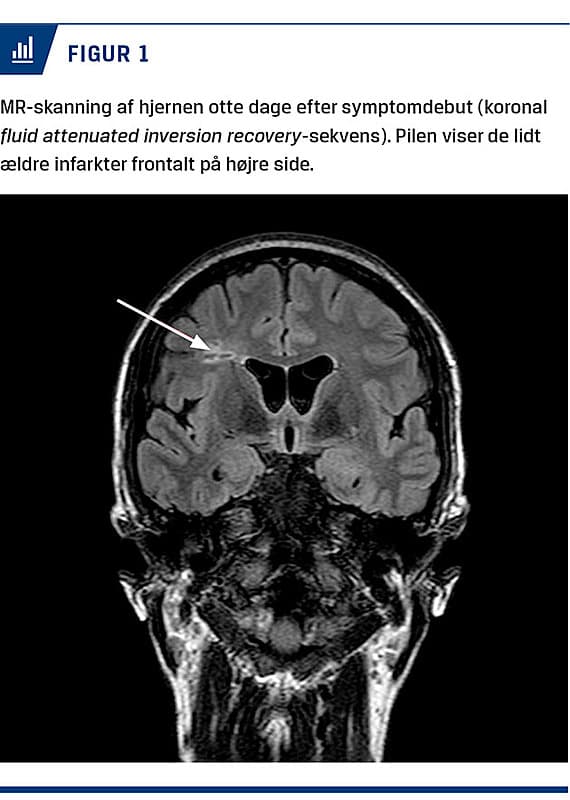

På mistanke om fokale anfald med påvirket bevidsthed blev der bestilt et elektroencefalogram (EEG) og MR-skanning af hjernen. Overraskende viste skanningen flere mindre, ældre infarkter subkortikalt i højre hemisfære (Figur 1). Desuden var der flere mindre hvid substans-forandringer end forventeligt for alderen.